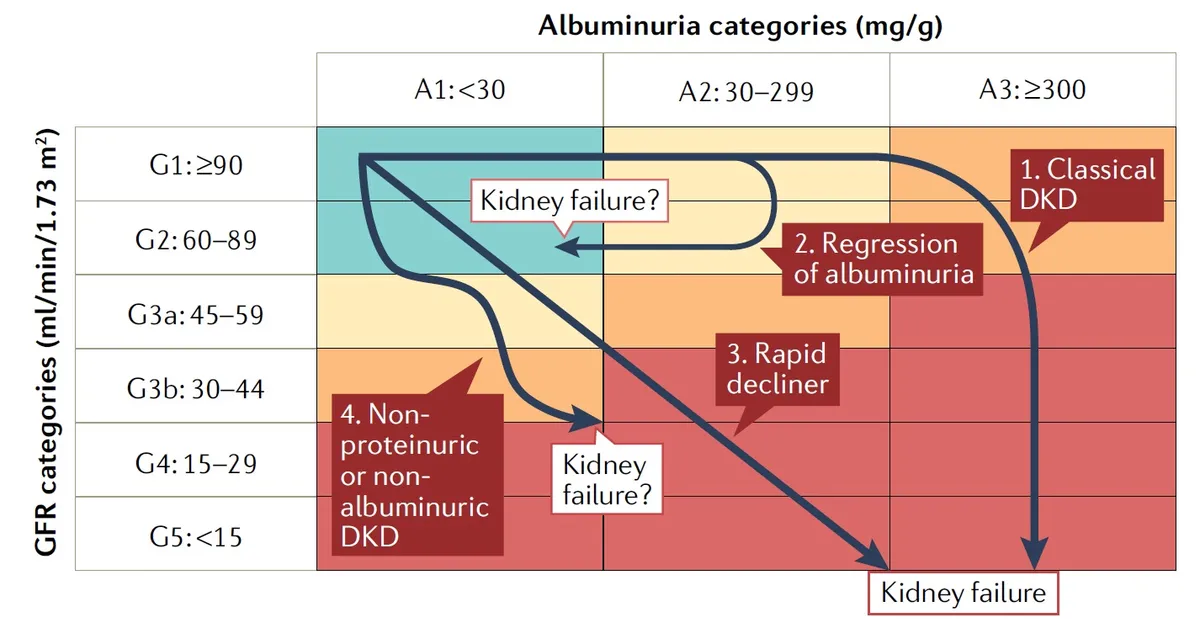

Injúria Renal Aguda (revisão Lancet 2025)

Injúria Renal Aguda (revisão Lancet 2025)